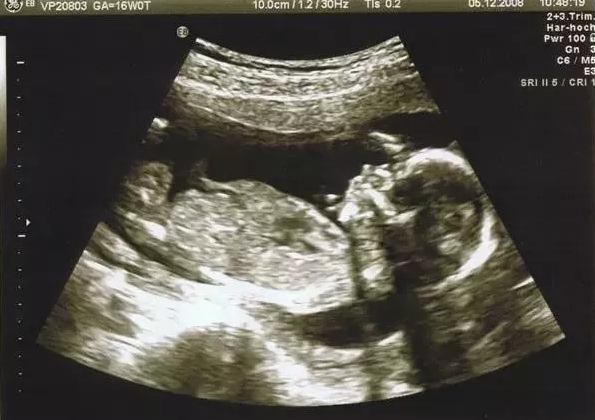

B超真的沒(méi)什么,準(zhǔn)媽媽懂了就好了?。?!

從準(zhǔn)媽媽得知自己懷孕的那一刻起,一大波孕檢項(xiàng)目就開始襲來(lái),其中B超是貫穿整個(gè)孕期的重要項(xiàng)目,可以幫助醫(yī)生和媽媽們更好了解寶寶的生長(zhǎng)發(fā)育情況。